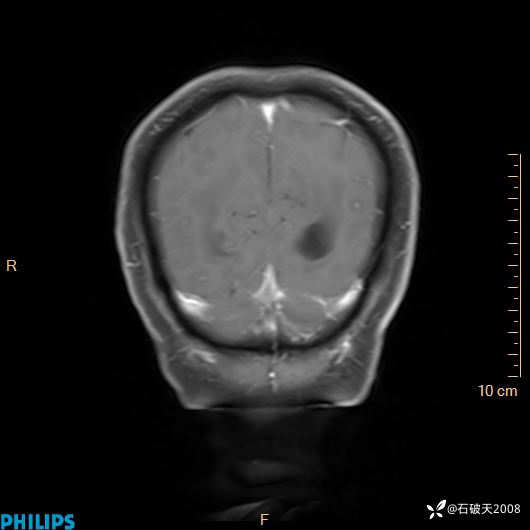

增强冠状位